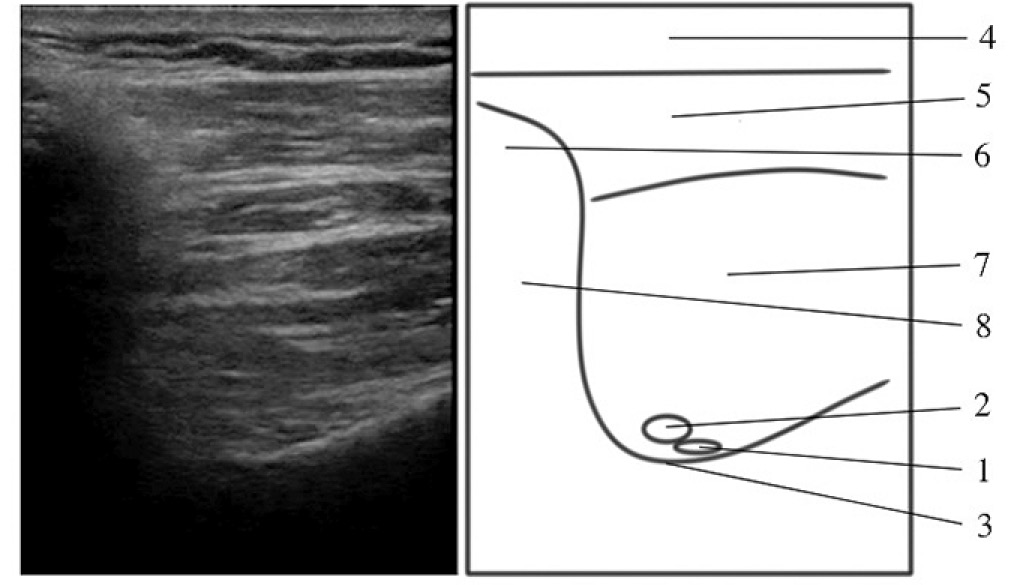

Пациент в положении лёжа на здоровом боку, оперируемая конечность сверху, плечо приведено, лежит свободно вдоль тела. УЗ-сканирование проводили в области надостной ямки лопатки, смещая датчик до визуализации вырезки лопатки, после чего датчик возвращали в исходное положение. Иглу вводили медиальнее датчика, подводя её кончик к надлопаточному нерву, ориентируясь на пульсацию надлопаточной артерии (анэхогенная, пульсирующая, несжимаемая, округлая структура) (рис. 3, 4). Для блокады надлопаточного нерва инъецировали 5 мл 0,75% раствора ропивакаина.

Рис. 3. Место блокады надлопаточного нерва в надостной ямке (плоскость сканирования дорсальнее плоскости, проходящей над вырезкой лопатки). 1 – надлопаточный нерв (место блокады), 2 – надлопаточная артерия, 3 – надостная ямка, 4 – подкожная клетчатка, 5 – трапециевидная мышца, 6 – ключица, 7 – надостная мышца, 8 – анэхогенная тень за ключицей